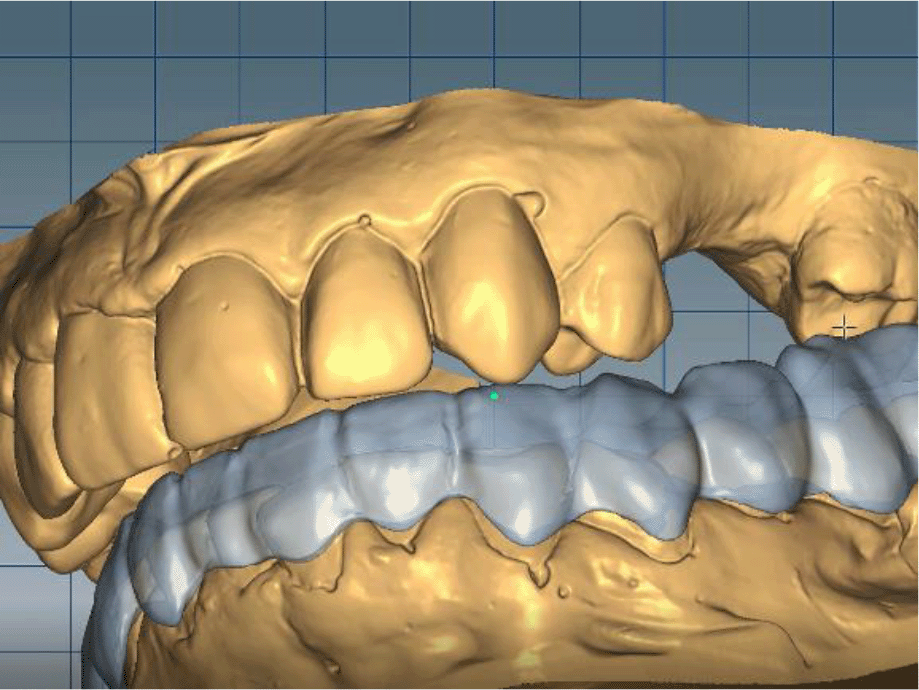

The cast gypsum models were scanned with a laboratory scanner and the obtained digital models were subjected to additional processing. Briefly, transfer of the morphological planning for the upper dentition (crown strategy) and for the lower dentition (digital wax up strategy, pontics) was performed (Figures 9 and 10).

26dd931c-41d3-478d-bec1-8cb211d0a4b8_figure9.gif

Figure 9. Clinical situation after upper preparation with increased VDO.

26dd931c-41d3-478d-bec1-8cb211d0a4b8_figure10.gif

Figure 10. Digital design on both jaws.